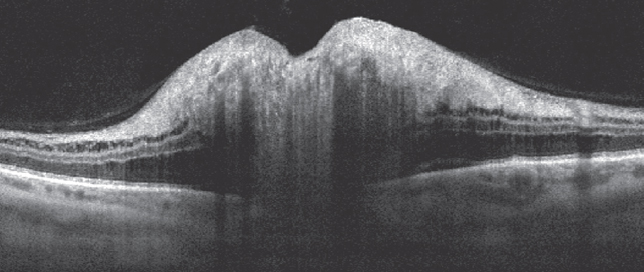

When comparing structural OCT of the macular area, there were no significant changes in both groups. There was neither IRF, nor SRF. At the same time, in the peripapillar zones in group 1 patients, a significant amount of IRF was detected, which in some cases, occupied a large area (Fig. 3). The maximal duration of the IRF presence was no more than 18 days.

Fig. 3. Intraretinal peripapillary fluid by оptical coherence tomography

Рис. 3. Интраретинальная перипапиллярная жидкость по данным оптической когенетной томографии